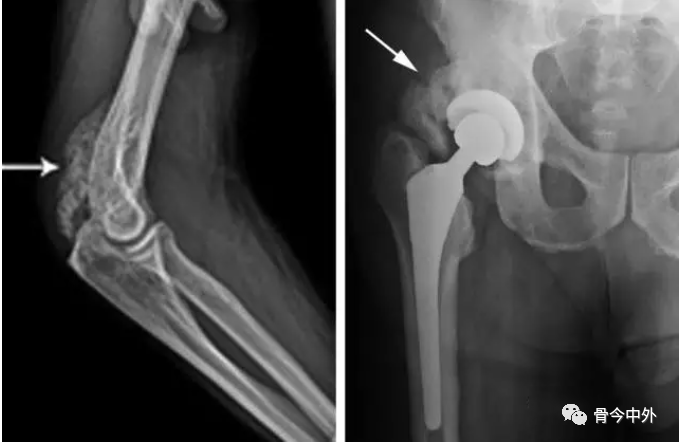

X 线检查是异位骨化最常见的检查方法,CT 更能清晰地发现早期成骨病灶。在疾病早期,仅表现为界限不清的软组织肿块,难以与炎症、血肿等疾病鉴别;随着骨化的成熟,X 线、CT 图像上逐渐出现点状钙化影,可出现特征性的「环状」「花边」或「蛋壳」样骨化,病灶周围呈软组织密度,这一影像征象有一定的特征性;晚期诊断困难较小,X 线平片和 CT 表现为软组织内团块状骨性致密影,为成熟的板层骨。如果持续随访,会发现病灶在6-7个月后持续缩小,最终可以看到骨小梁影。

左图:X 线显示线状钙化影 (左蓝色箭头)。右图:随访 4 个月,可见钙化增多 (红色箭头),符合异位骨化。

脊髓损伤患者的HO极少发生于上肢关节。创伤性HO可位于关节旁或将关节包绕,而神经损伤性HO则往往位于关节旁。在创伤骨科中,尤以髋臼骨折和肘关节骨折最为多见。关节置换术后以及严重的长骨骨折后异位骨化发病率为3%~20%。

髋臼骨折和肘部骨折所致异位骨化最为常见,髋臼骨折内固定术后大约40%患者形成异位骨化。Guo等推荐髋臼骨折手术采用粗隆翻转或者后侧入路,异位骨化在粗隆翻转、前路手术及后路手术的发生率分别为33.3%、42.1%和36.9%

肘关节骨折后异位骨化的的发病率约为40%,异位骨区常位于肘关节后内侧。20%以上肘关节异位骨化患者,肘关节屈伸活动度减小,其活动度<100°。